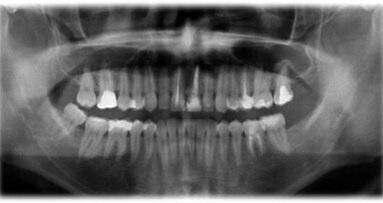

Pacjentka narzekała głównie na kolor oraz przerwy między zębami w odcinku przednim górnego łuku (Ryc. 2-6). Po zebraniu wywiadu medycznego oraz stomatologicznego wykonano badanie kliniczne i radiologiczne w celu ustalenia rodzaju problemu (związek z próchnicą, problem natury periodontologicznej lub endodontycznej).

Podczas wywiadu stomatologicznego pacjentka przyznała, że miesiąc wcześniej leczono ją periodontologicznie i że pozostała pod obserwacją na Wydziale Periodontologii. Co więcej, wspomniała, że nosiła aparat ortodontyczny przez ponad 5 lat i że nie chciała kontynuować leczenia. Ortodonta stwierdził, że pacjentka nie była współpracująca, jeśli chodzi o wymianę ligatur oraz że nie pojawiła się na kilku wizytach mimo odklejonych zamków, nie utrzymywała też wystarczającej higieny jamy ustnej. Dodatkowo, oczywistym było przeciwwskazanie do kontynuacji leczenia ortodontycznego ze względu na ryzyko resorpcji korzeni spowodowane długotrwałą aktywacją aparatu.

Badanie kliniczne wykazało niski poziom higieny jamy ustnej, przerost dziąseł, widoczne przebarwienia wokół zamków z powodu palenia tytoniu, próchnicę w prawym górnym kle oraz koronę na metalu na zębie 22 (Ryc. 2-6). Po zdjęciu zamków wykryto niewielka demineralizację szkliwa wokół nich. Zauważono też przesunięcie linii pośrodkowej łuku górnego w stosunku do linii pośrodkowej twarzy (Ryc. 1). Badania kliniczne i radiologiczne nie wykazały nieprawidłowości w odcinkach bocznych.